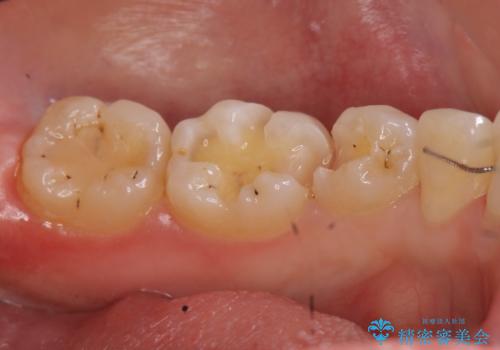

- 奥歯の歯と歯の間が虫歯になっていました。

セラミックインレーで治療しました。